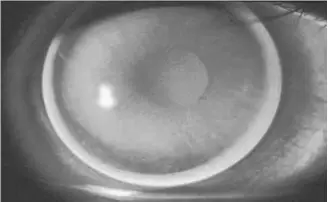

- (B) 螢光圖顯示中央大片亮區(明顯淚液池化)、周邊均勻亮邊——典型的**過陡(steep fit / apical clearance)**圖型,整體圓形分布,無散光特徵。